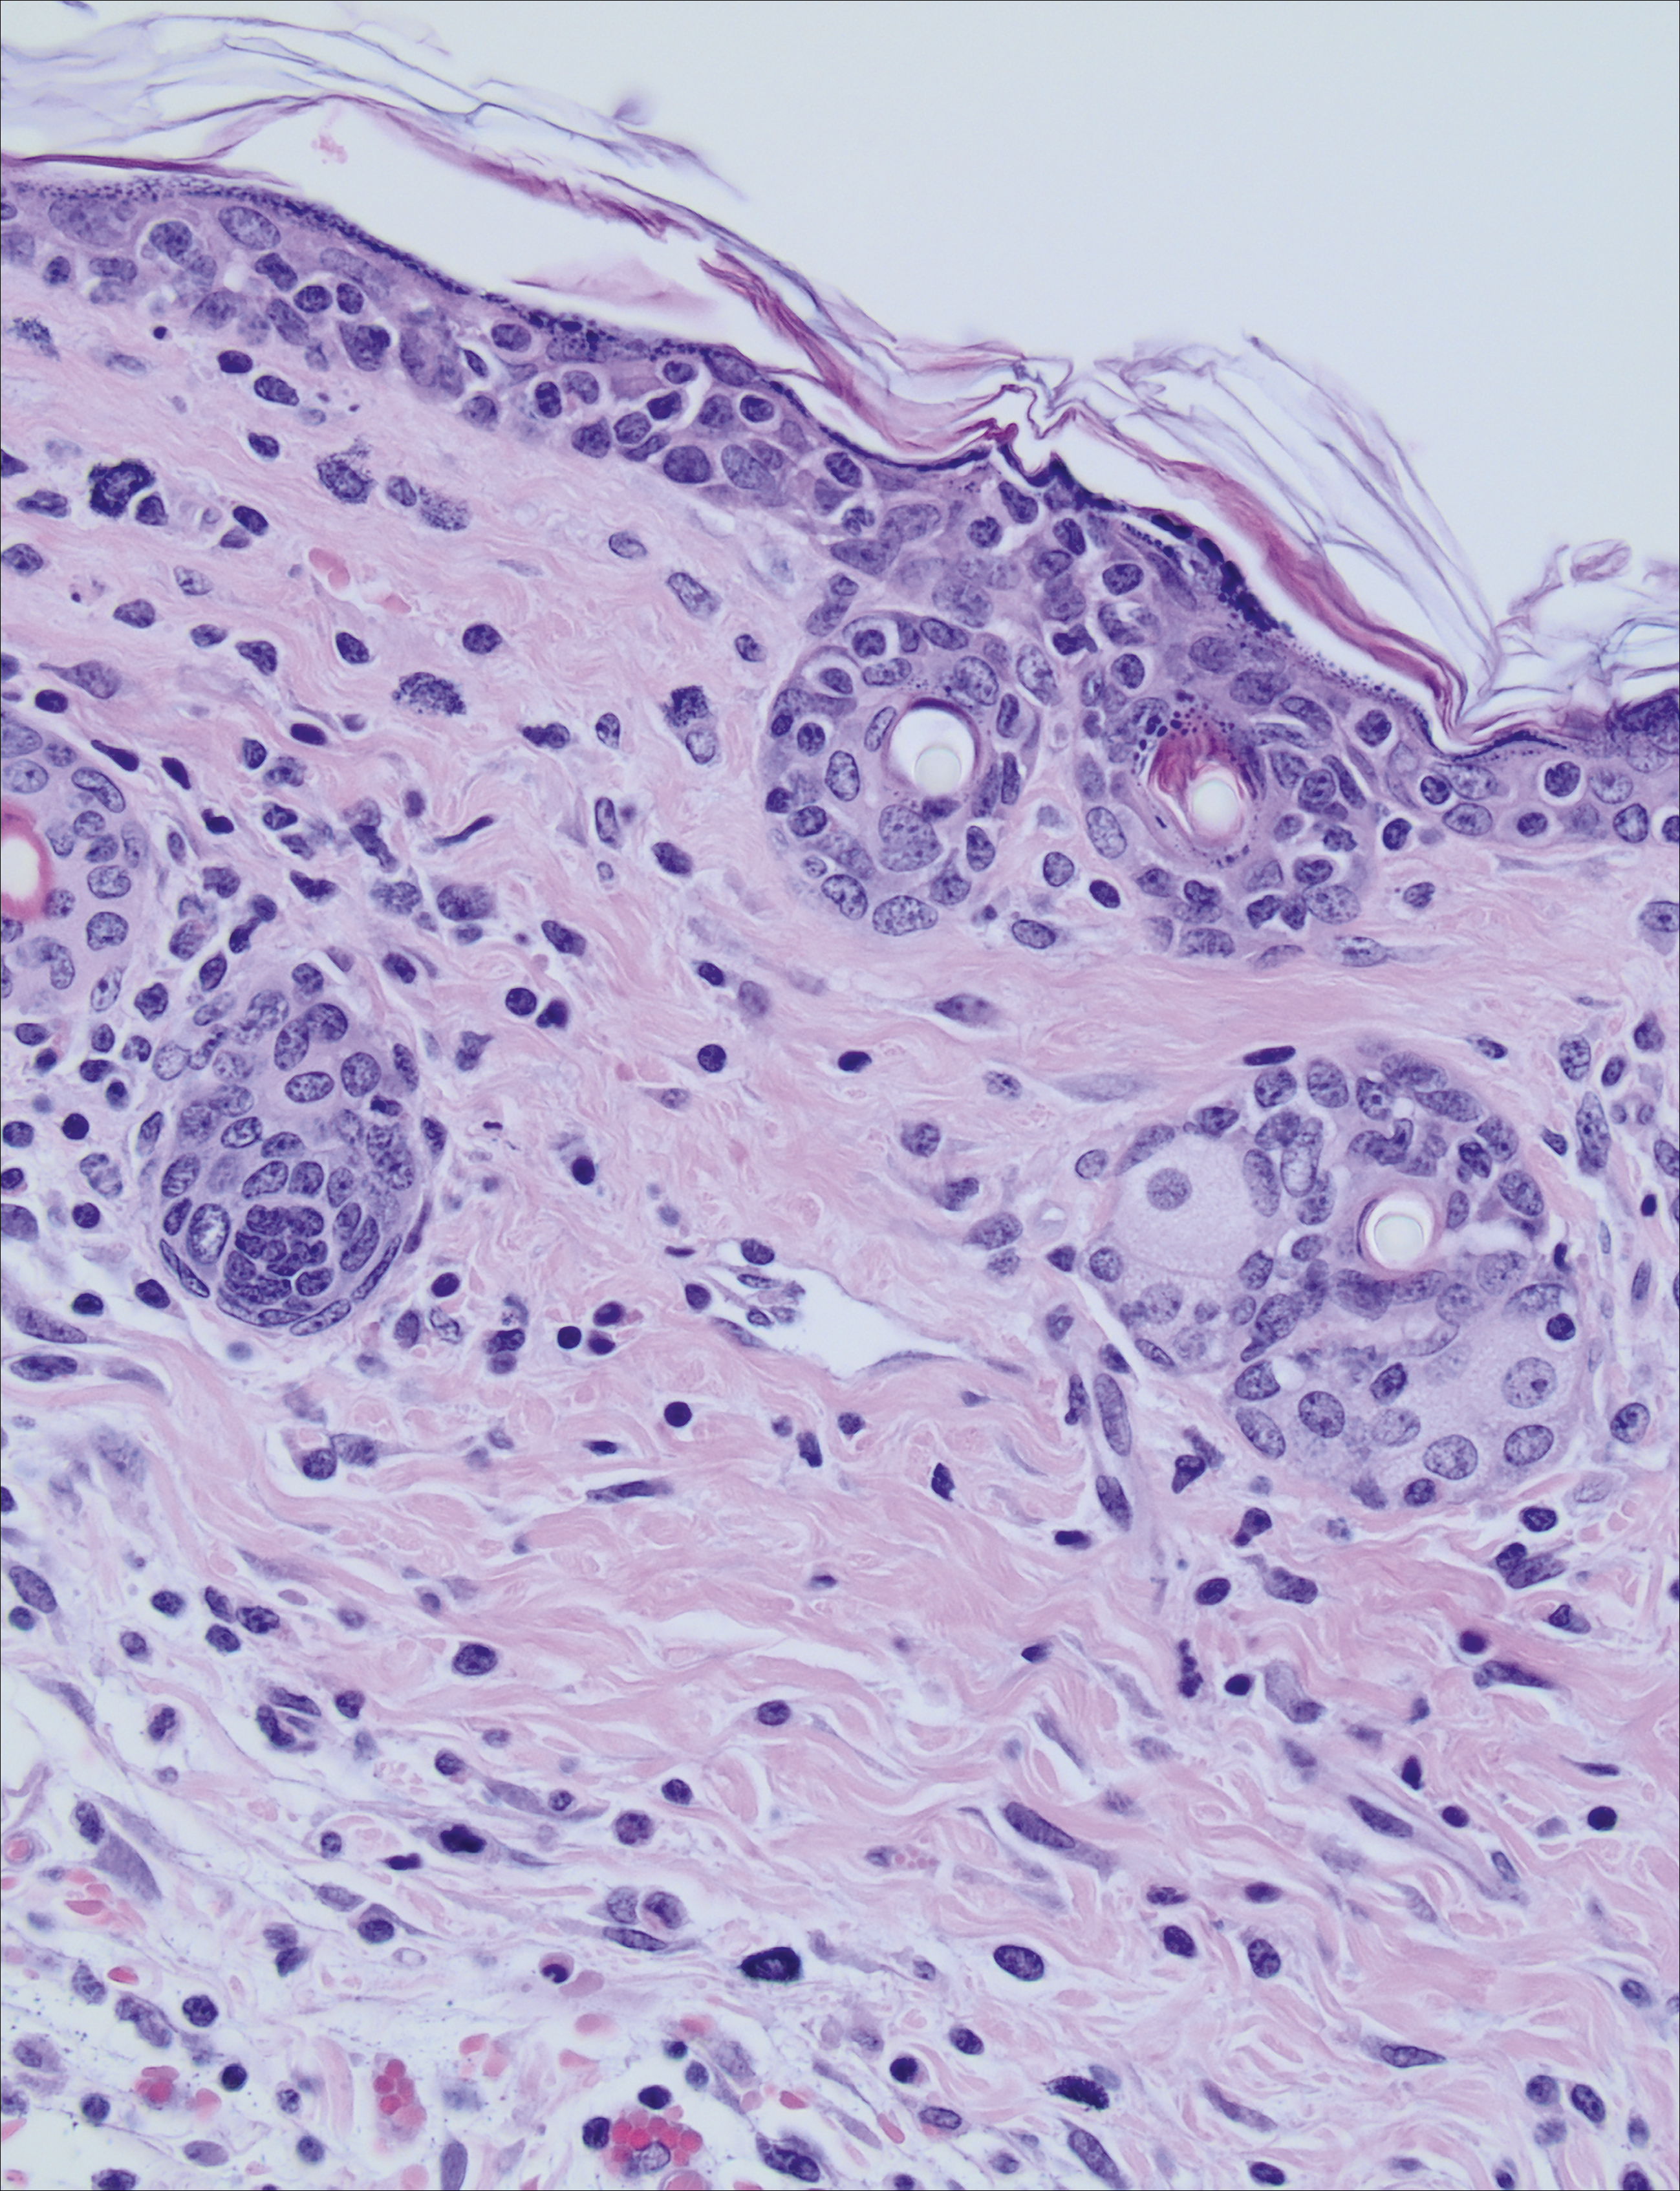

Hematoxylin and eosin–stained skin tissue from an interleukin-15–transgenic mouse. Notice the epitheliotropic lymphocytes that are characteristic of cutaneous T-cell lymphoma, for which this mouse is a useful model. Bortezomib treatment results in therapeutic benefit compared with vehicle treatment. See the article by Kohnken et al on page 771.